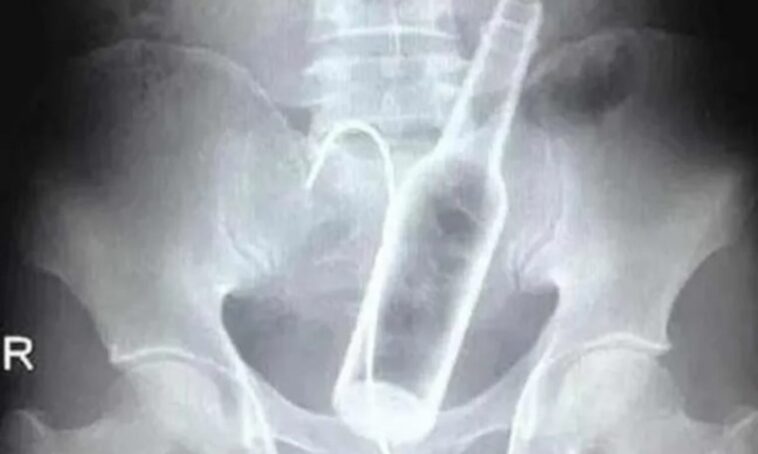

Você já imaginou que um simples objeto poderia transformar uma vida em um pesadelo de hospital? Pois é, mais de 4 mil pessoas por ano são levadas ao pronto-socorro por causa de objetos “presos” no ânus. E, para quem achava que esse tipo de situação era algo raro, um caso recente ocorrido em João Pessoa, na Paraíba, ilustra de forma dramática essa realidade. Na terça-feira (14/1), um homem de 60 anos deu entrada no Hospital de Emergência e Trauma Senador Humberto Lucena com um objeto de quase 1 metro de comprimento introduzido em seu próprio ânus. O cenário, no mínimo, constrangedor, exigiu uma cirurgia de laparotomia (abertura da cavidade abdominal) para a remoção do item. Apesar da gravidade, o paciente está estável e segue sob observação médica. Curiosamente, ele não soube dizer como o objeto foi parar ali, o que só aumenta o mistério em torno desses acidentes inusitados.